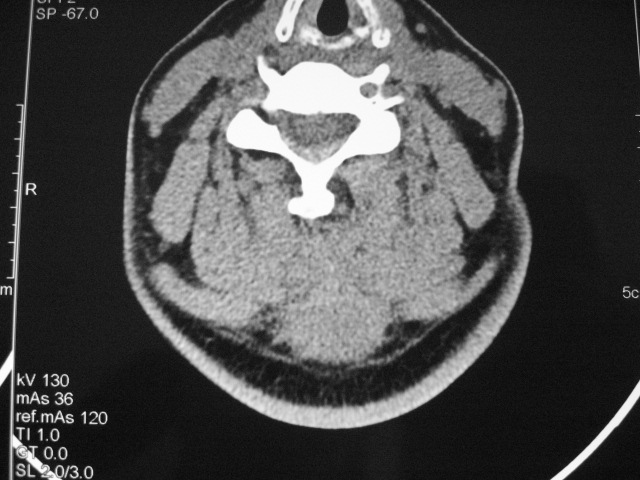

女,46岁,发现颈后区肿块3月余.

颈后软组织肿块,内可见坏死区及点状钙化,邻近颈椎棘突可见破坏,邻近肌间隙模糊,肿块周围脂肪间隙可见索条状影。

考虑:1)感染,结核可能;

2)肿瘤不能排除。

考虑:起源于项韧带的硬纤维瘤可能性大,建议活检进一步检查。

颈后部结核性脓肿可能性大,侵犯临近颈椎棘突,建议进一步检查并照胸片。